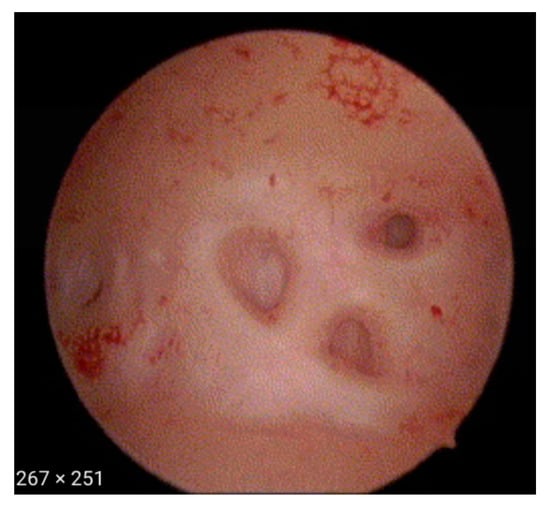

- Irregular endometrium with tiny openings seen on the endometrial surface (Figure 1)

- Hypervascularisation (Figure 2)

- An endometrial “strawberry” pattern (Figure 3)

- Fibrous cystic appearance of intrauterine lesions (Figure 4)

- Haemorrhagic cystic lesions presenting with a dark blue or chocolate brown appearance (Figure 5)